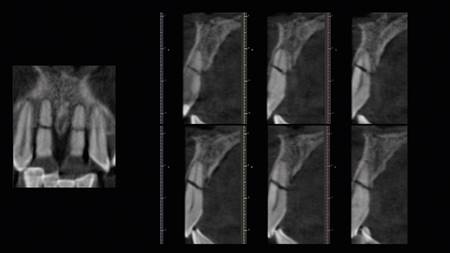

Hombre de 42 años, sistémicamente sano, asiste al Departamento de Implantología de la Universidad de Los Andes. El examen clínico y radiográfico evidenció desdentamiento parcial superior e inferior. La evaluación periodontal mostró una periodontitis crónica generalizada. Se confirmaron fracturas asintomáticas de ambos incisivos centrales superiores en el tercio medio radicular, con leve desplazamiento coronal y movilidad clase II (Fig. 1). La primera etapa terapéutica consistió en la realización de tratamiento periodontal e instalación de una prótesis parcial removible. Se indicó la toma de un examen Cone Beam CT.

Posteriormente se realizó una impresión de alginato y vaciado en yeso del maxilar, se eliminaron mecánicamente ambos incisivos centrales. Este modelo se digitalizó con un escáner extraoral (3Shape, Trios) y se obtuvo un archivo STL. Luego con esto datos se hizo una coincidencia digital entre el CBCT y el archivo STL, utilizando el software BlueSky plan, (BlueSky bio). Se planificaron dos implantes cónicos de conexión interna de 3.8 x12 mm (Biohorizons), separados de la parte vestibular de las raíces y asegurando su correcto posicionamiento implantario (Img 1). Luego se diseñó una guía quirúrgica en el mismo software, exportada e impresa en ácido poliláctico (PLA) por una impresora de tecnología de deposición de material fundido (FDM) (Duplicator 7, Wanhao, China). Después de la anestesia local, se extrajo la porción coronal de ambos dientes fracturados, luego las partes apicales restantes se dividieron mesio-distalmente con una fresa de diamante de alta velocidad dejando dos porciones. Se retiró la parte palatina y se conservaron 5 mm de la pared vestibular radicular, posteriormente se instaló la guía quirúrgica en posición (Fig 2 y 3).